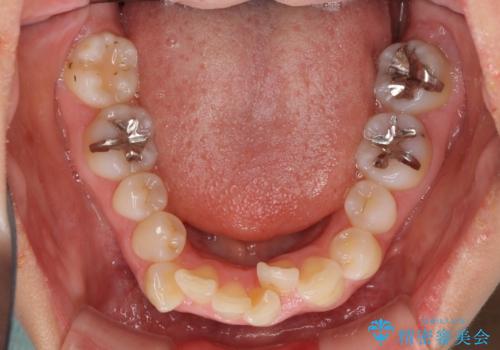

デコボコで飛び出した前歯 ワイヤー装置による抜歯矯正

- 上下前歯のデコボコと、飛び出した前歯を気にして来院された患者様です。

口元を積極的に引っ込めるために、上下左右の小臼歯計4本を抜歯することとしました。

矯正治療前の咬み合わせで、前歯がすり減ってしまい、歯列が整ったときに先端がガタガタになってしまったため、矯正治療後に形態修正を行いました。